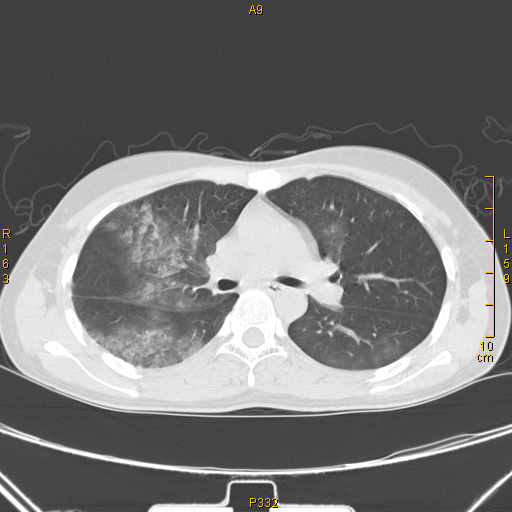

吸入性肺炎 (co中毒后误吸致右侧肺炎)